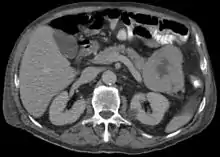

ترتبط سرطانة الخلايا العنيبية بزيادة الليباز في مصل الدم ويتجلى في الشكل الكلاسيكي مثل ثالوث شميد (نخر دهني تحت الجلد، التهاب المفاصل، فرط الحمضات)،[3] تكون سرطانة الخلايا العنيبية كبيرة قد تصل إلى 10 سم ولينة مقارنة بسرطانة البنكرياس الغدية لأنها تفتقر السدى الكثيف، ويُمكن أن تنشأ في أي جزء من البنكرياس.[2]

عادةً ما يظهر الفحص المجهري الضوئي لخزعة سرطان الخلايا العنيبية مظهرًا حبيبيًا، وعادة ما تكون الكيمياء النسيجية المناعية إيجابية بالنسبة للتربسين والكيموتريبسين والليباز. في الاختبارات الجينية يُعثر على الجينات/البروتينات المعدلة لـ بي53 وSMAD4 وبروتين داء السلائل القولوني الورمي الغدي وARID1A وGNAS.[5]